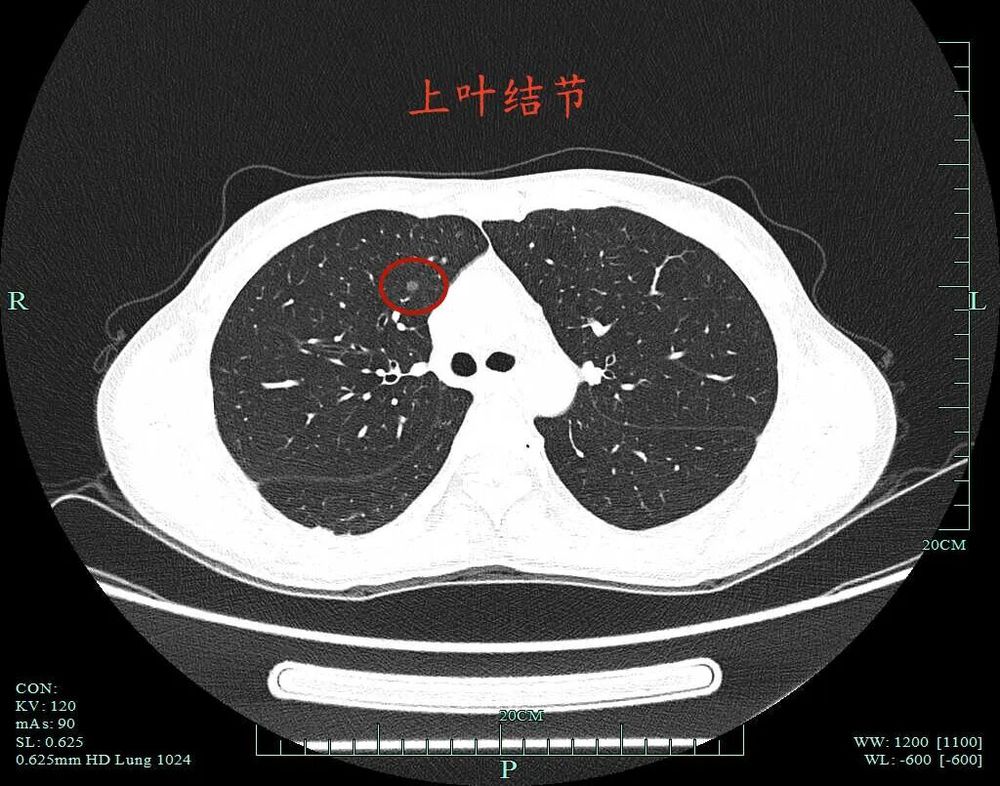

指南上说优先处理主病灶,兼顾次病灶,在不影响生存及符合无瘤原则前提下尽量切除病灶并尽可能保留肺功能。次病灶若是纯GGO,受限于心肺功能无法全部切除时,建议6-12个月随访1次。也就是说:如果心肺功能吃得消,即便次病灶是纯GGO,也是应该尽量切除。这个原则也是宣扬“一网打尽”处理肺结节的医生的指导性原则。但我总觉得指南也是人定的、脱胎于临床研究与回顾分析得出的结论肯定会落后于疾病的发展与时代的变化、疾病谱的改变,从而不一定适应临床。死守指南会导致患者肺功能受损明显、创伤太大、费用过高,而且无法解决导致多发病灶的机体内环境与外环境因素,从而难以避免后续随访中再检出新的病灶。所以我一直宣扬“抓大放小”。今天分享的这个病例右侧较为明显的有四处病灶,主病灶A在右下叶靠近叶间裂,次病灶一处在右上叶病灶B,一处在右下病灶C,还有一处密度很淡的病灶D是邻近病灶B的。我们是如何决策与考虑的?

上叶病灶B也是磨玻璃密度的,轮廓与边界清。

上叶病灶D邻近病灶B,但太微小,也很淡。